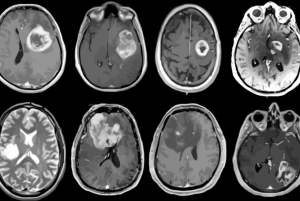

Jenis Tumor Otak Berdasarkan Tingkat Keganasannya

Tumor otak adalah pertumbuhan abnormal sel-sel di dalam otak yang dapat menjadi baik (non-keganasan) atau ganas (keganasan). Jenis tumor otak dapat diklasifikasikan berdasarkan tingkat keganasannya.